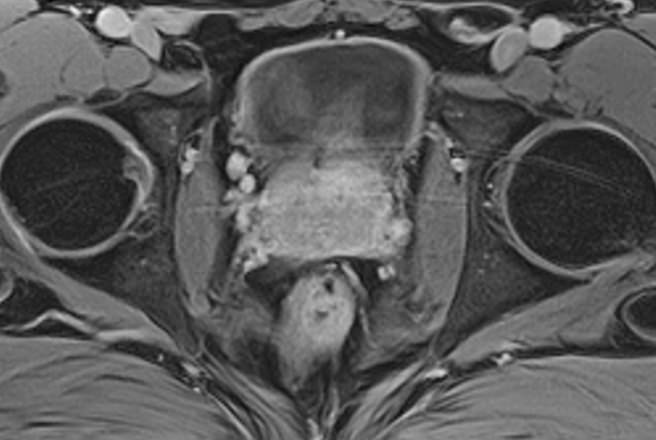

МРТ мочевого пузыря позволяет найти причины возникновения вышеперечисленных симптомов, выявить патологические изменения в мочевом пузыре, окружающих органах и тканях, поставить точный и достоверный диагноз. Процедура безболезненна и при отсутствии противопоказаний безопасна. Метод МРТ не предусматривает использование вредного рентгеновского излучения, поэтому может проводиться неоднократно в течение короткого периода времени, что, например, бывает важно для оценки эффективности лечения.

Но несмотря на высокую диагностическую ценность магнитно-резонансной томографии, в некоторых случаях для улучшения визуализации патологических очагов дополнительно применяется контрастное усиление. В частности, при подозрении на опухолевые образования мочевого пузыря (как первичные, так и метастатического происхождения) требуется внутривенное введение контраста.

Для контрастирования применяются контрастные препараты, содержащие соли парамагнетика гадолиния (Омнискан, Магневист, Гадовист и др). Контрастное вещество попадает в кровоток, что позволяет оценить степень васкуляризации тканей и выявить очаги поражения, в первую очередь, опухолевых новообразований, причем на самых ранних стадиях развития.

Проведение МРТ с контрастированием, в первую очередь, применяется в онкодиагностике. Метод позволяет детально визуализировать опухоль, ее локализацию, размеры, степень прорастания в окружающие ткани, оценить стадию развития. Кроме того, МРТ незаменима в сложных диагностических случаях, при получении неоднозначных противоречивых данных предыдущих обследований.